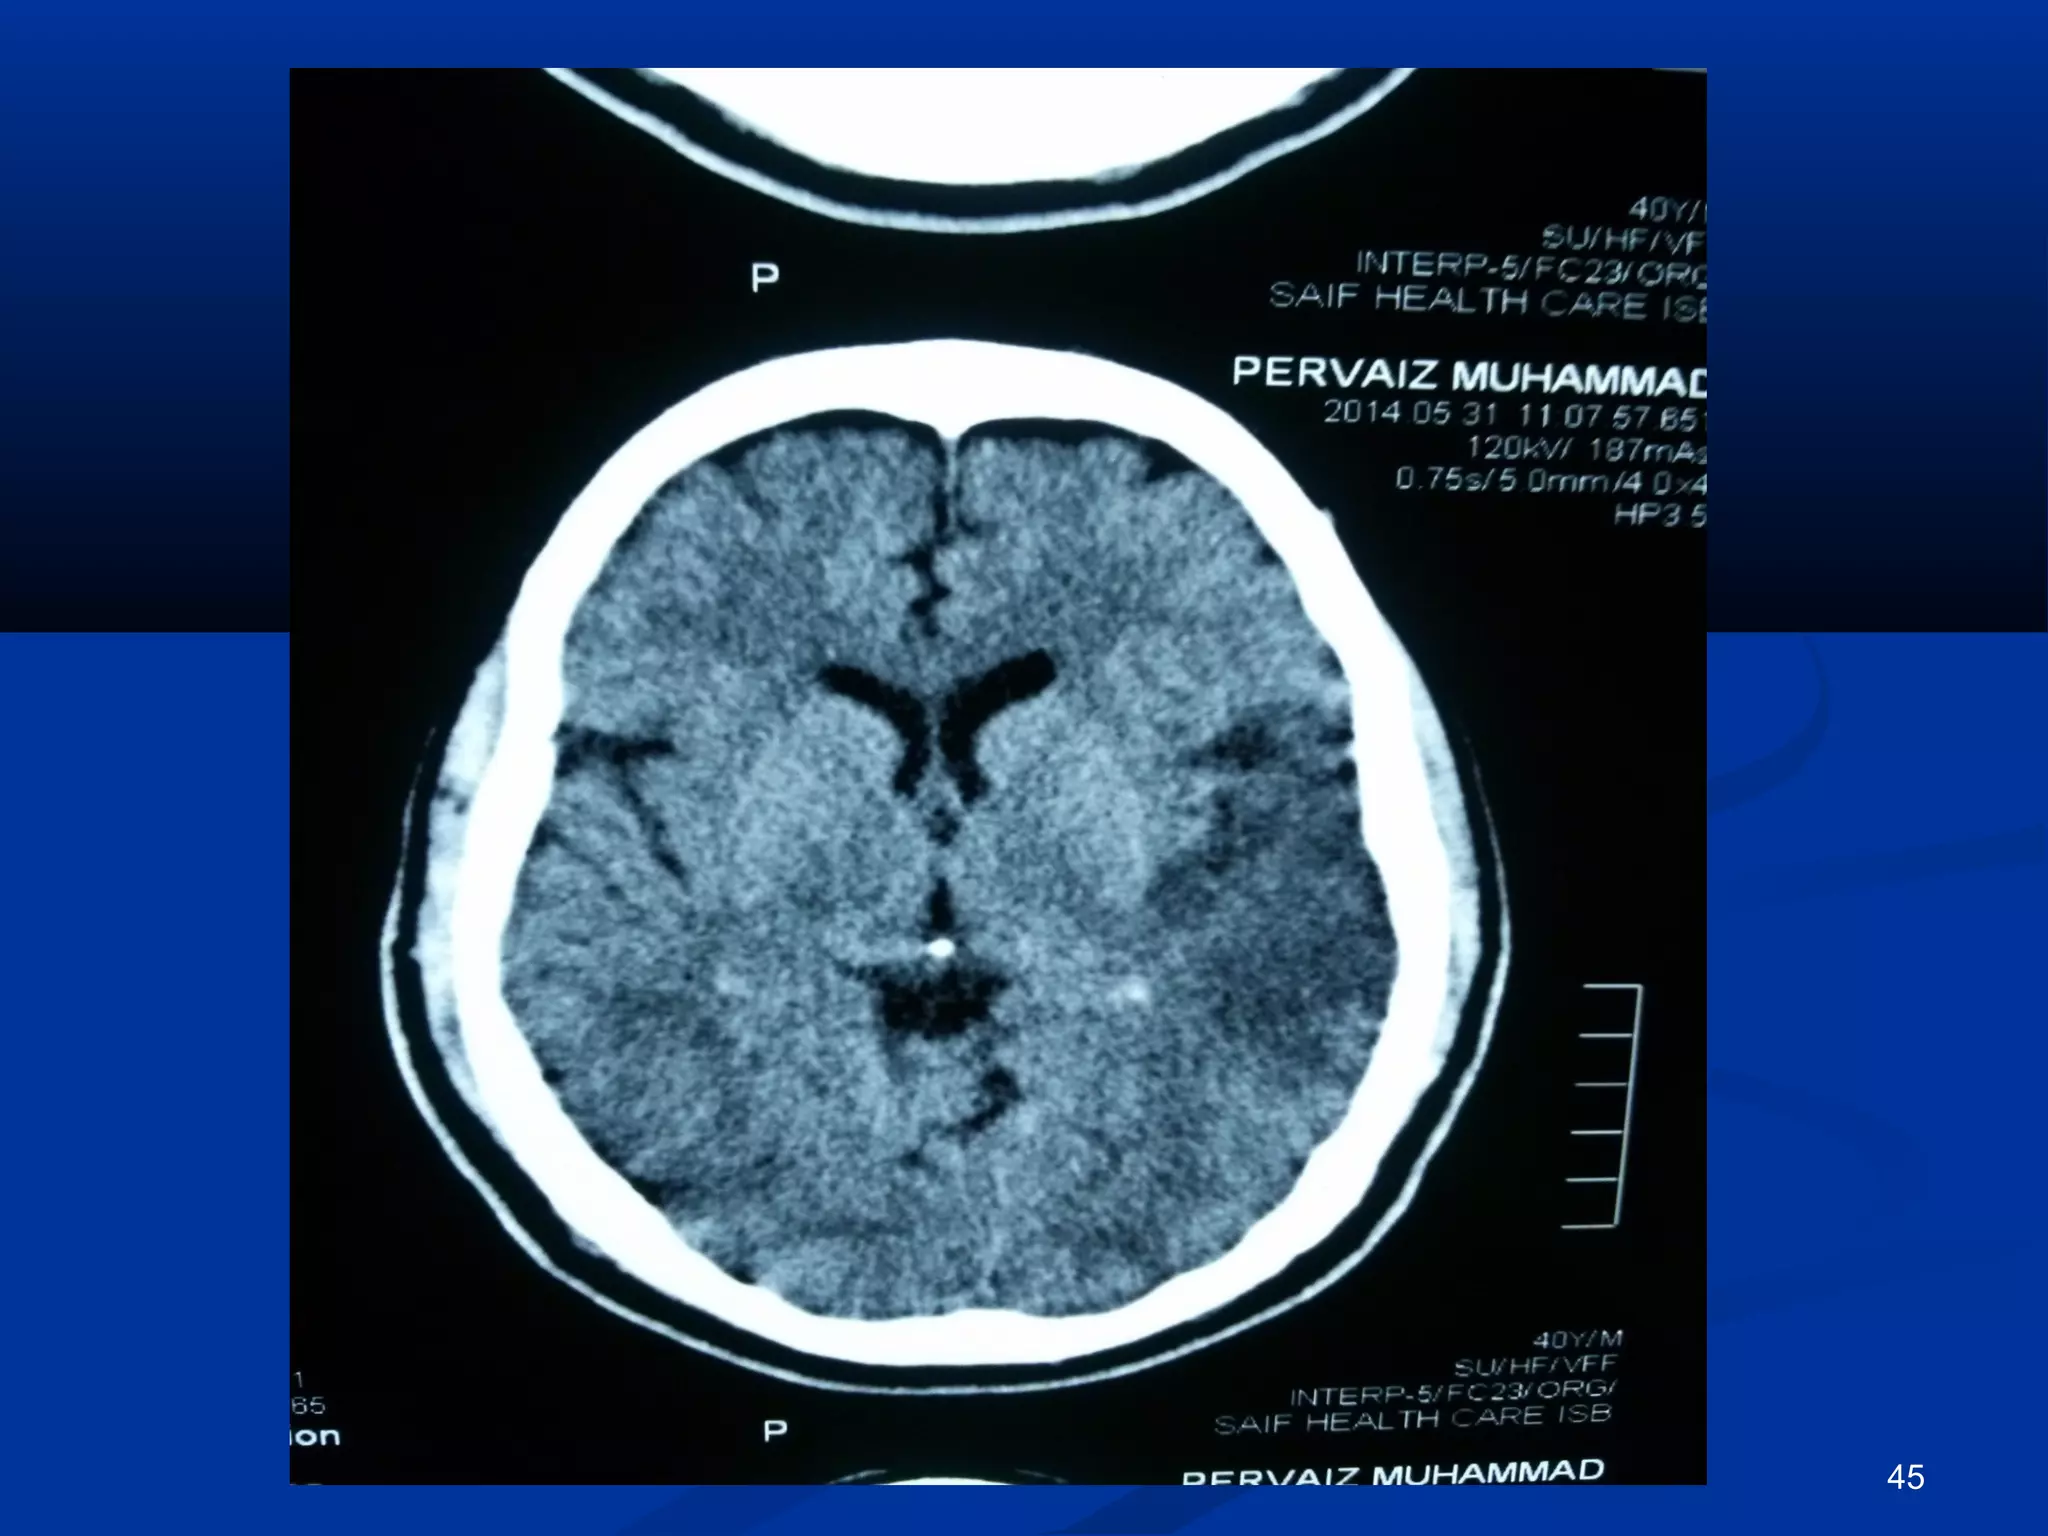

CCTT..bbrraaiinn

45

 CCTT.. bbrraaiinn,, EECCHHOO,, aanndd DDoopppplleerr II sshhoowweedd yyoouu.. 50